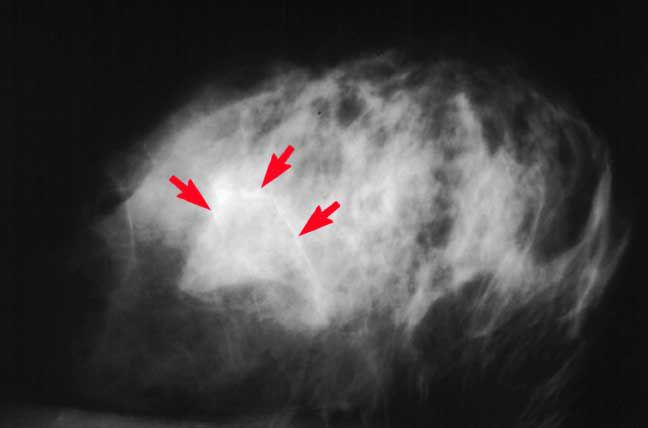

They appear as white spots or flecks on a mammogram but can't be felt during a breast exam. Symptoms like chest pain usually don’t happen until you’ve had it for a while. Stenting is an approach to help open blood vessels that have become too. Calcifications can form in many places throughout your body, including:

Calcified synonyms, calcified pronunciation, calcified translation, english dictionary definition of calcified. They appear as white spots or flecks on a mammogram but can't be felt during a breast exam. Information and translations of calcify in the most comprehensive dictionary definitions resource on the web. Calcified opacities is a radiological term that means there was an area that appeared opaque in that the rays could not penetrate there, and it appeared like bone. Calcified Triticeous Cartilage Detected on Digital Panoramic.

Breast calcifications are calcium deposits that appear as white dots on a mammogram. To make or become stony or chalky by deposition of calcium salts. Success rates are high, but there are risks with each treatment. Shell internal, chiefly membranous, with calcified nucleus, nautiloid; The calcified lung nodule What does it mean? ScienceOpen.